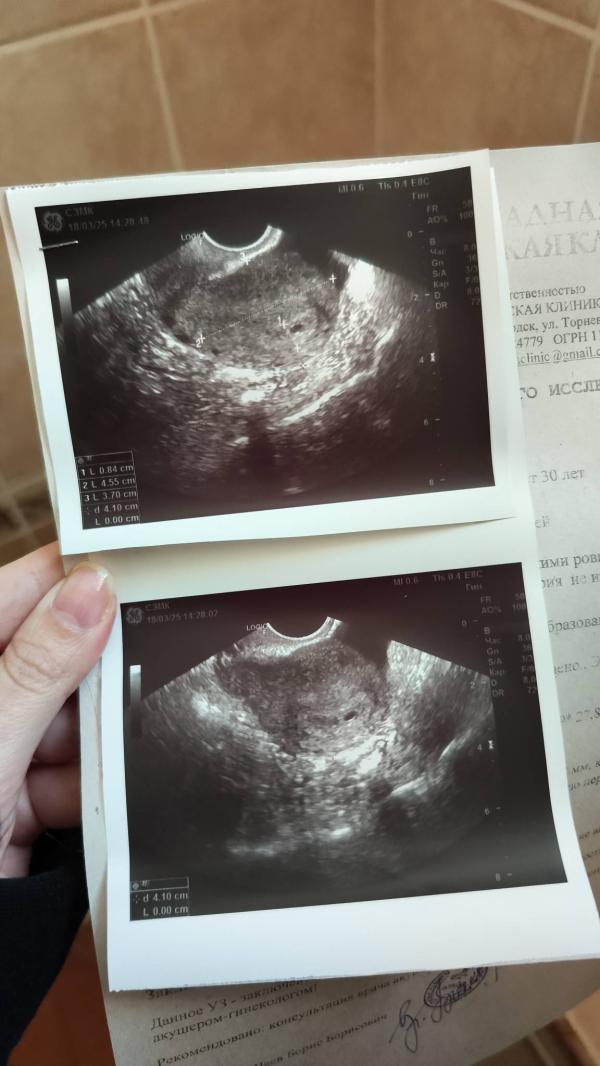

Маточная беремность, плодное яйцо на 2-3 недели. Ну теперь жду недель 7-8, чтобы определить сердцебиение и на учёт)

Поздравляю, сколько мм пя?🤗